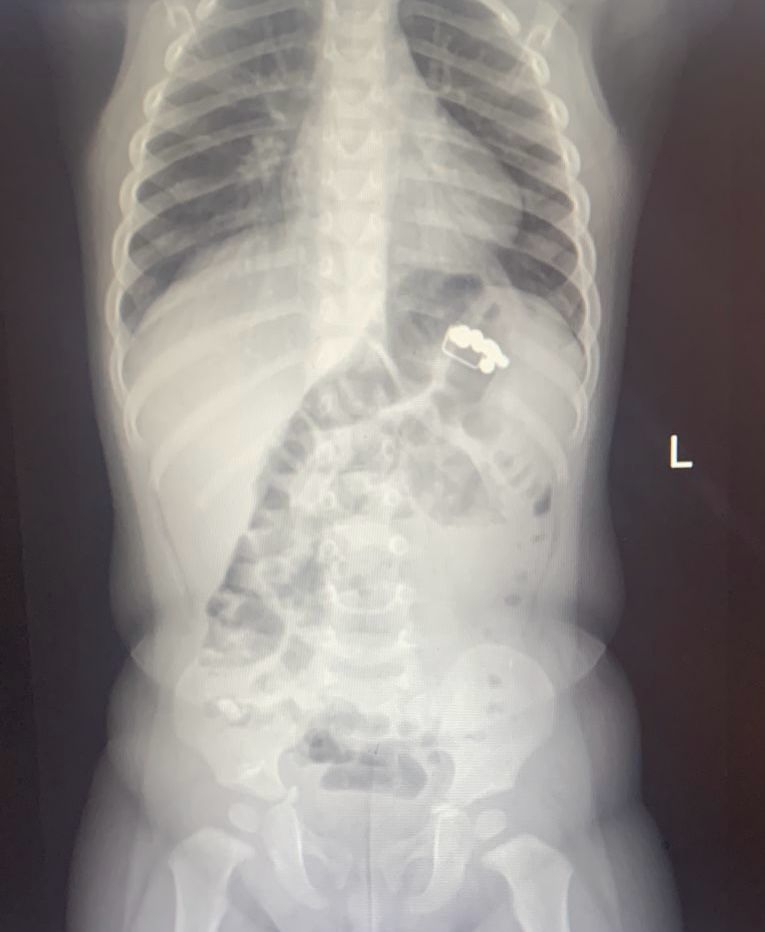

Много было и хорошего в сфере здравоохранения. Не проходило и дня, чтобы медики не сохраняли кому-то жизнь. Врачи спасали 66-летнего местного жителя с тромбом в сонной артерии, помогали женщинам после сложных операций родить здоровых деток, собирали воронежцев после серьезных травм, применяли инновационные методы лечения, возвращали слух, проводили уникальные операции, доставали из людей самые невероятные предметы, такие как крест, восстанавливали откусанный язык, заводили сердце пациенту, перенесшему инфаркт, возвращали с того света тех, кто пережил клиническую смерть, внедряли современный метод лечения мочекаменной болезни, запускали остановленное сердце, извлекали пулю в миллиметрах от спинного мозга, совершили настоящие чудеса!

А сколько детей спасли воронежские медики! Малыши глотали магниты, канцелярские кнопки, гайки, монеты и батарейки. Все это (и не только) извлекали из маленьких пациентов в 2025 году.